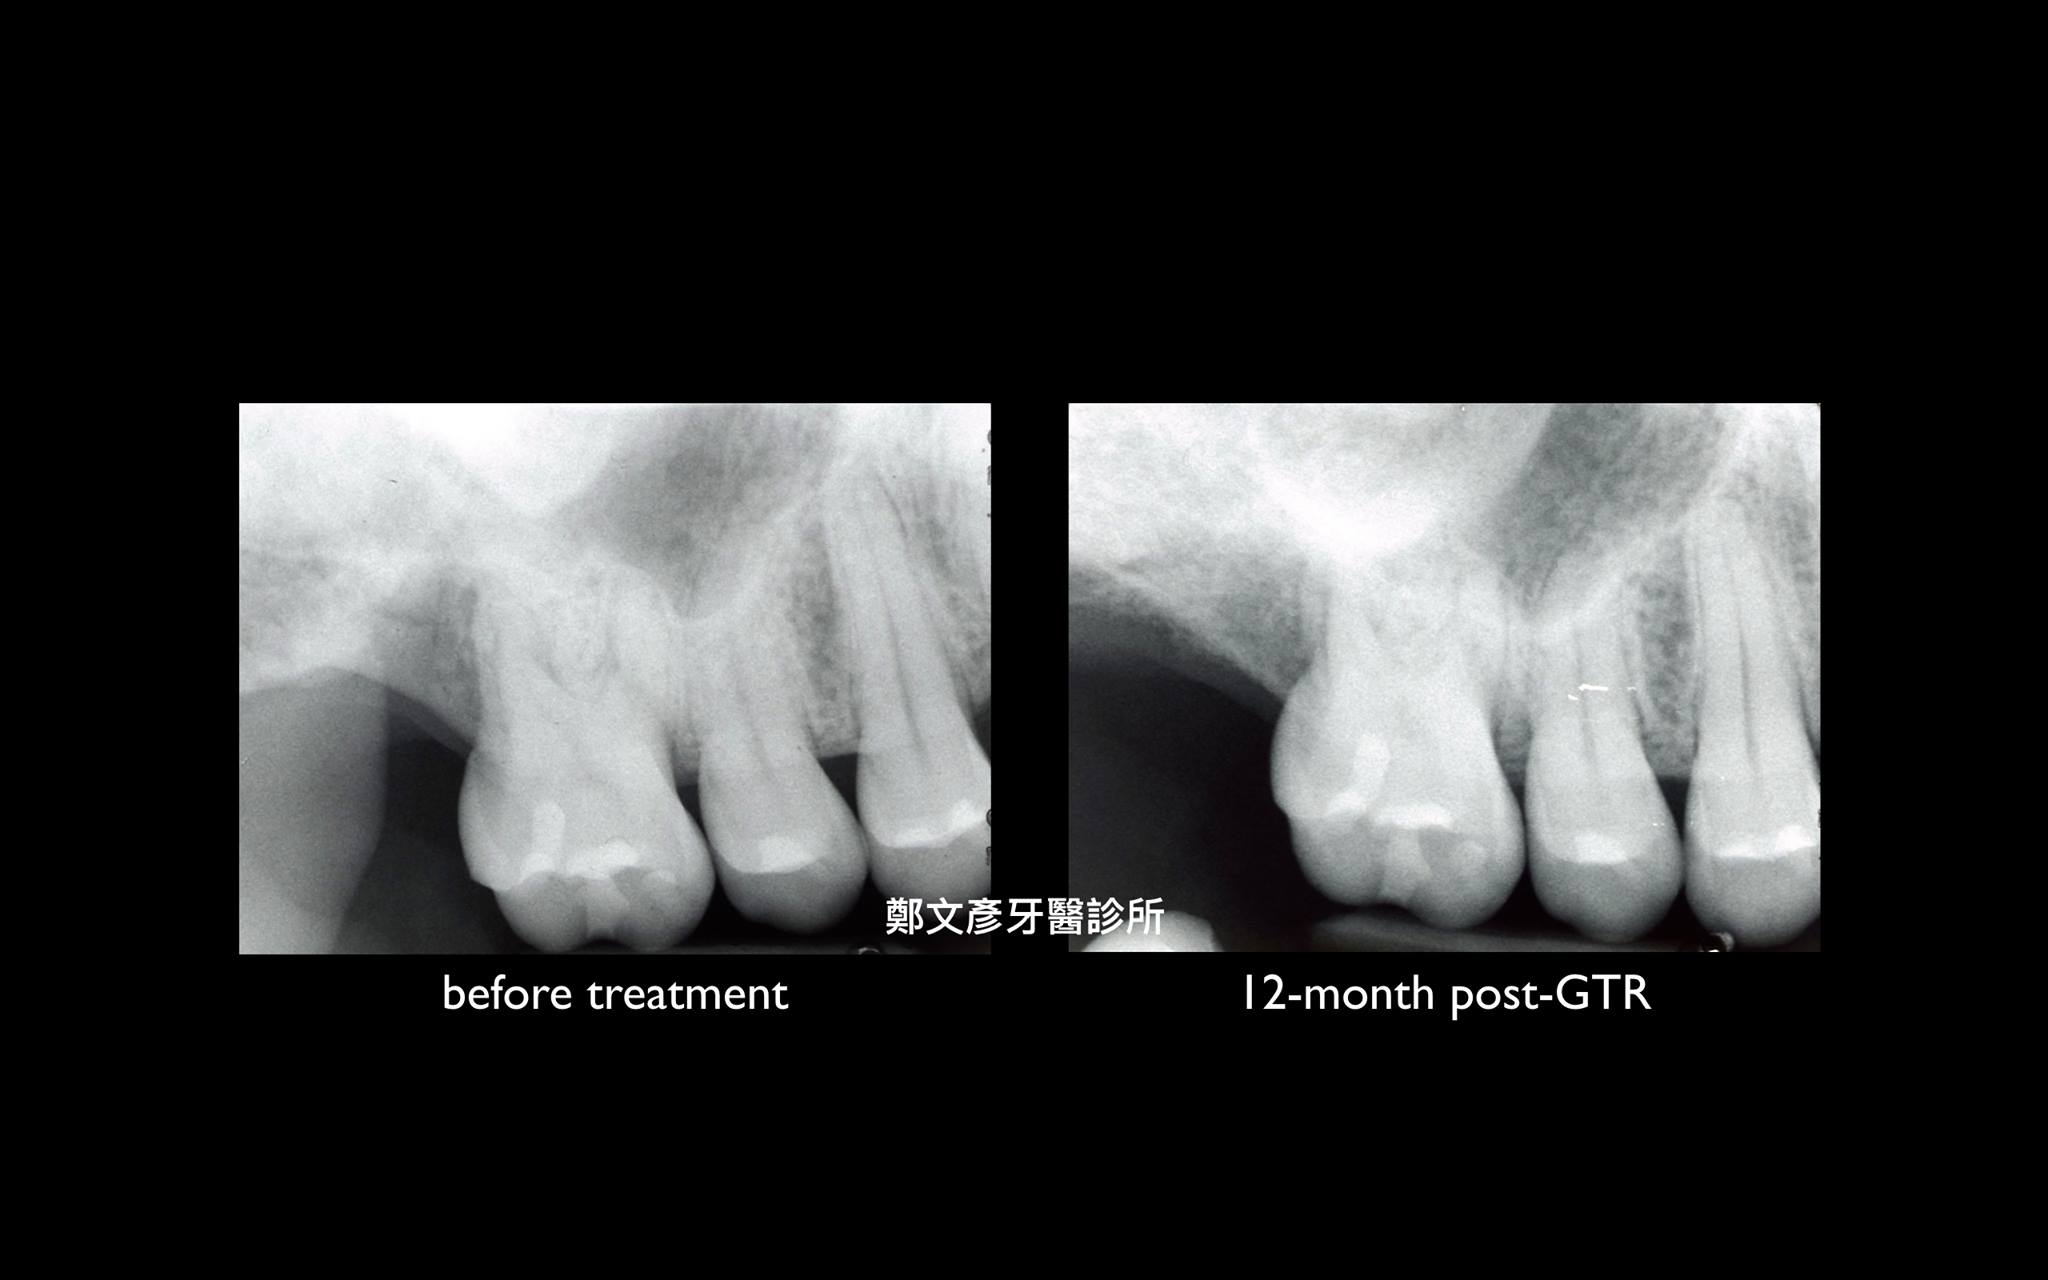

牙周再生補骨手術 ( GTR )

再生補骨